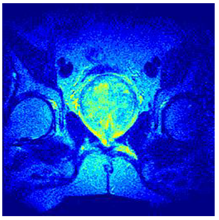

Table 5 presents the segmentation of the MRIs using EO for a qualitative inspection. From Figure 5, it is clear that two lumps in the prostate have been highlighted by the thresholding process. Prostatic MRIs present noisy conditions, which makes it difficult to visualize the thresholding with the naked eye, so in Figure 5 we present the thresholded image as well as the histogram with the values of the thresholds generated by the EO. It can be observed in the histogram that the thresholds present an adequate distribution, even though this particular image has impulsive noise and a simple shape. Our findings indicate that four thresholds are typically sufficient for this application, which corresponds to identifying five different tissue types in the image. A smaller threshold value may result in a lack of sufficient contrast to highlight relevant anatomical structures, such as the prostate capsule. In contrast, a higher number of thresholds may lead to the incorrect differentiation of anatomical regions that should be connected.

Table 5.

Segmentation of transaxial-cut prostate MRI images Using EO and cross-entropy. This table presents the segmentation results of transaxial-cut prostate MRI images using the equilibrium optimizer (EO) and cross-entropy. Each row corresponds to a distinct MRI image, while the columns nt represent the number of thresholds applied during segmentation. The results illustrate the performance of the EO algorithm across different threshold levels for each image.